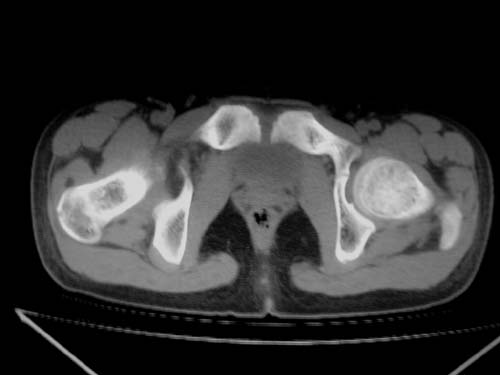

标题: CT19608:女12岁,左髋部疼痛,无发热病史 [打印本页]

标题: CT19608:女12岁,左髋部疼痛,无发热病史

左股骨干增粗,磨玻璃样改变——考虑骨纤维异常增殖症!

左股骨干增粗,磨玻璃样改变——考虑骨纤维异常增殖症!骨化性纤维瘤?